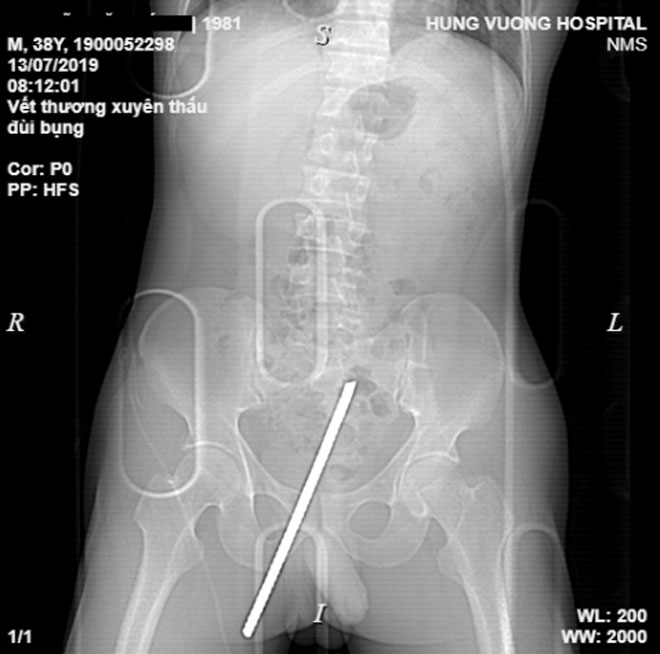

Hình ảnh phim chụp cho thấy thanh sắt suýt xuyên thấu "của quý" nạn nhân

Kết quả chụp chiếu cận lâm sàng của bệnh nhân cho thấy hình ảnh dị vật kim khí trong phần mềm dưới da vùng bẹn mu bên phải, sát dương vật, xuyên chéo lên đi dọc theo thành bụng dưới rốn trái.